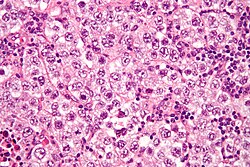

| Embryonal carcinoma | prominent nucleoli, vescicular nuclei | var. arch.: tubulopapillary, glandular, solid, embryoid bodies (ball of cells in surrounded by empty space on three sides), +/-nuclear overlap, mitoses common | CD30 | usu. part of a mixed GCT | |